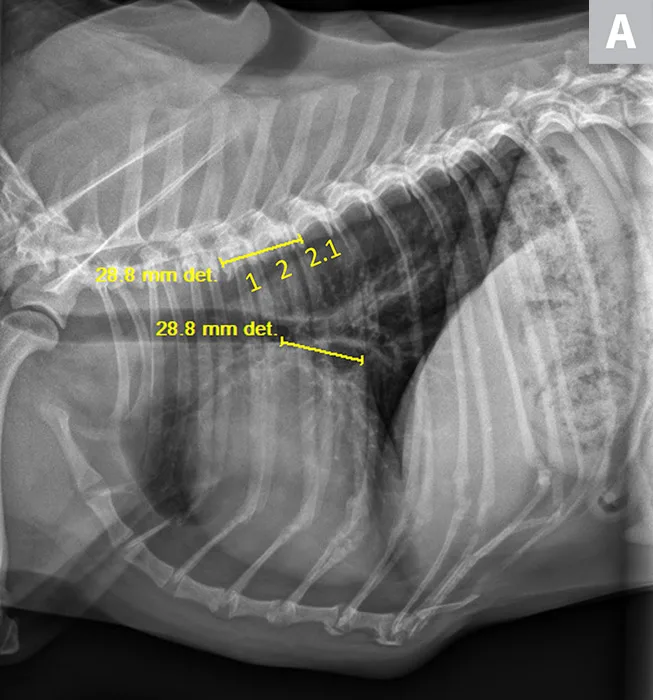

Thoracic radiographs revealed mild, generalized cardiomegaly (Figure 1). VHS was 11 (normal for Cavalier King Charles spaniel, 10.1-11.1).13 VLAS was 2.1, suggesting no left atrial enlargement. Based on physical examination and radiographic findings, stage B1 MMVD was suspected. Although medical therapy was likely unnecessary, monitoring was needed, and evaluation for further thoracic radiograph changes and clinical signs consistent with heart failure (eg, increased respiratory rate, coughing, exercise intolerance, collapse) was needed.

FIGURE 1

VLAS measurement in a dog with suspected stage B1 MMVD using a left lateral radiograph (A). A caliper was used to measure from the center of the most ventral aspect of the carina to the most caudal aspect of the left atrium, where it intersects with the dorsal border of the caudal vena cava. This measurement was transferred to the cranial aspect of T4 and extended caudally along the thoracic vertebrae. The number of vertebrae this line transversed was rounded to the nearest tenth to determine VLAS (2.1 VBUs). Stage B1 MMVD was confirmed via echocardiography. A redundant dorsal tracheal membrane, gastric food/foreign material, and mild T3 to T4 spondylosis deformans can also be seen. An orthogonal radiograph of the patient provides a more complete evaluation of cardiac silhouette (B); normal location of the left atrium is indicated (circle).